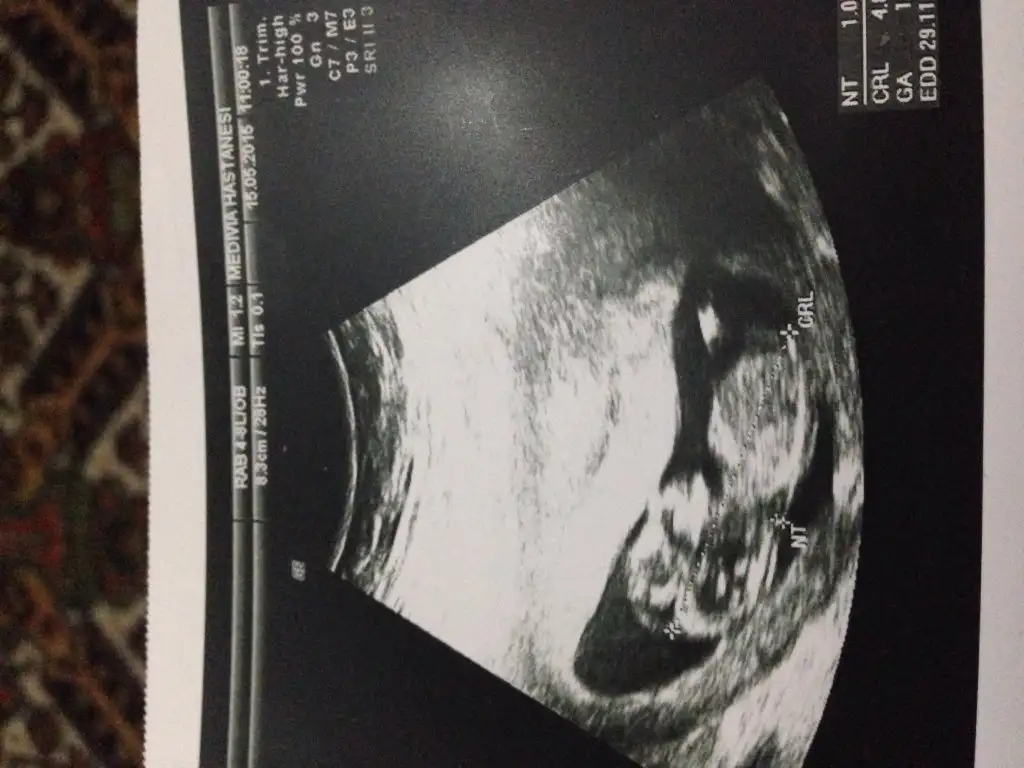

Canım doktorun erkek dediği resmi de koyar mısın?Bebeğimin cinsiyeti belli oldu ERKEK